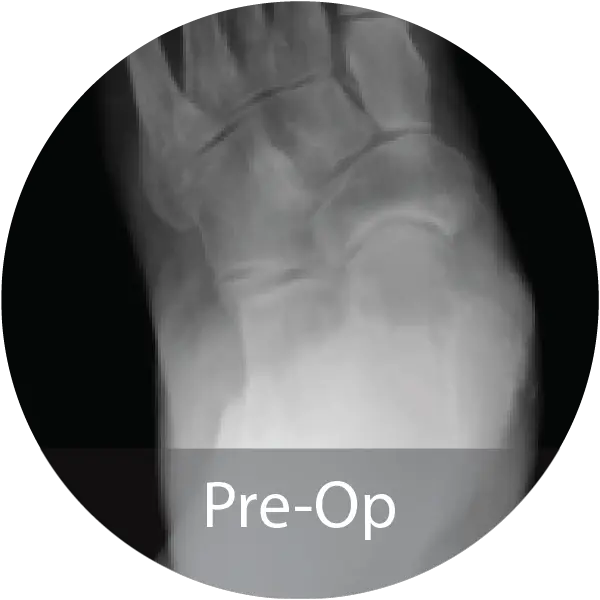

FOOT & ANKLE

Case of 64-year-old female with hindfoot arthritis treated with tibiotalocalcaneal arthrodesis and intramedullary nailing using InduceXT®. Reported solid osseous consolidation with no postoperative complications, pain-free ambulation, and full return to activities.

Case of 74-year-old female with hallux rigidus and multiple metallic allergies treated with 1st MTPJ arthrodesis using biointegrative hardware and InduceXT® hydrated with normal saline. Reported complete osseous consolidation at 12 months and pain-free outcome.

Case of 68-year-old female with post-traumatic osteoarthritis treated with subtalar joint arthrodesis using InduceXT®. Reported successful fusion at 12 months with no postoperative complications, pain-free ambulation, and return to normal activities.

Case of 79-year-old male with progressive collapsing foot deformity and secondary ankle osteoarthritis treated with triple arthrodesis and total ankle replacement using InduceXT®. Reported solid osseous fusion with well aligned hindfoot and ankle, no pain during ambulation, and full return to activities.